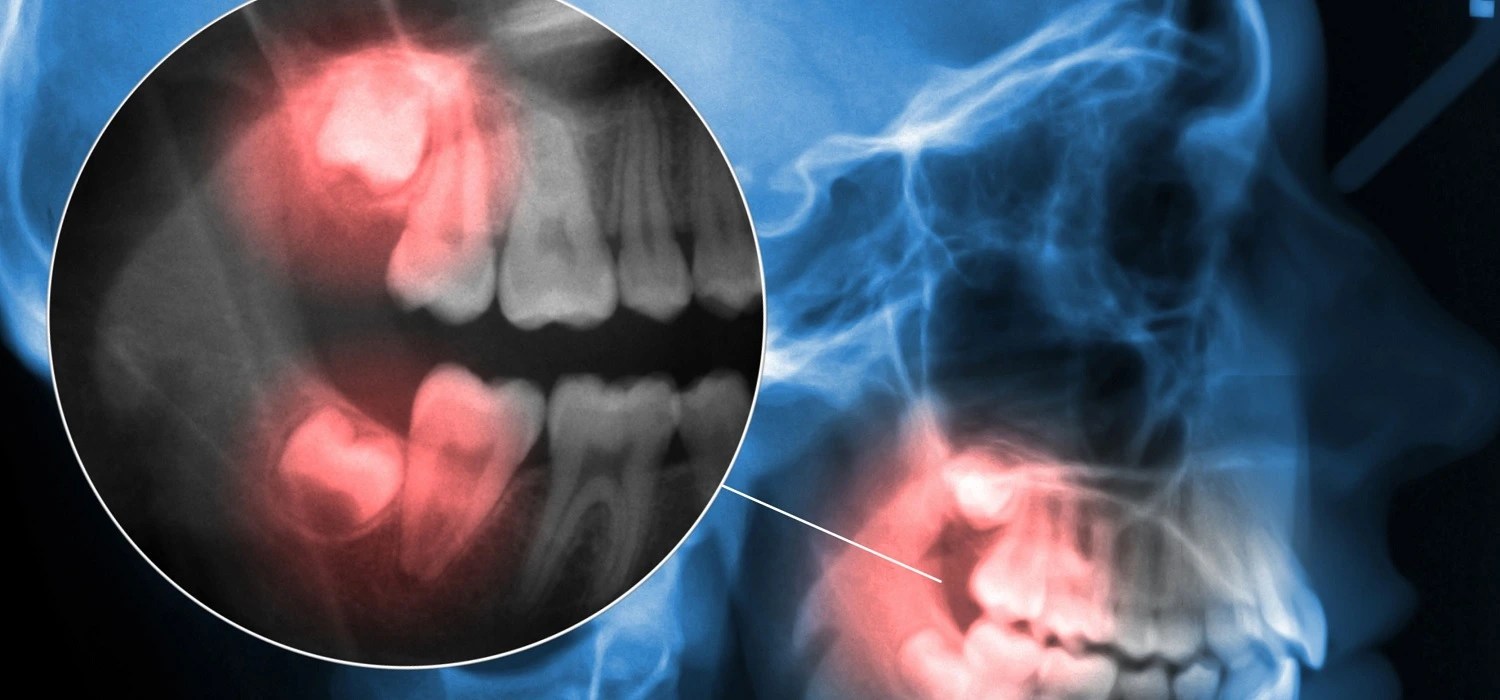

Osteomyelitis of jaw

Panoramic dental Xray showing right mandibular osteomyelitis (“lumpy Osteomyelitis From Tooth Infection Infections can also begin in. If the tooth is the source of infection,. In this case report, we review the diagnosis. Garre's osteomyelitis is a local thickening of the periosteum caused by a slight irritation or infection. Among these, three cases of mandibular osteomyelitis were associated with tooth decay and bisphosphonate or radiation. Advise the patient to maintain local hygiene. Osteomyelitis From Tooth Infection.